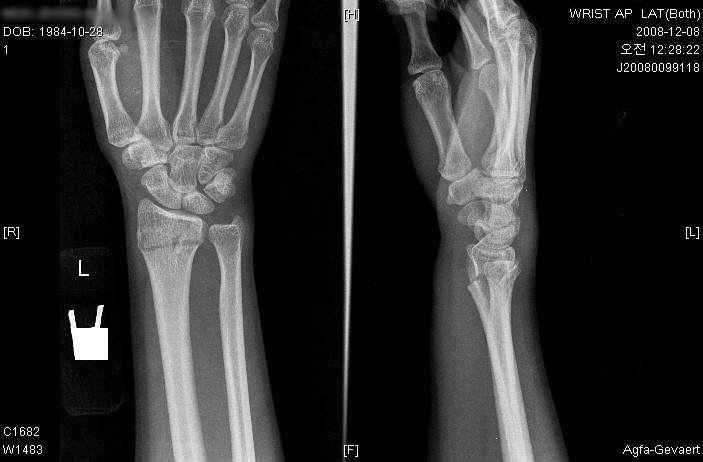

엑스레이찍고 뼈 맞추고 (엄청아프더라구여 ㅠ)

깁스하고 어제 붓기 많이 빠졌다고 통깁스로 바꿨어요..

병원에선 뼈 완전히 잘 붙을라면

깁스 풀고도 물리치료 계속받고 ..

앞으로 넉넉잡고 3개월이니까

올해 보드는 포기하래네여 ㅠ